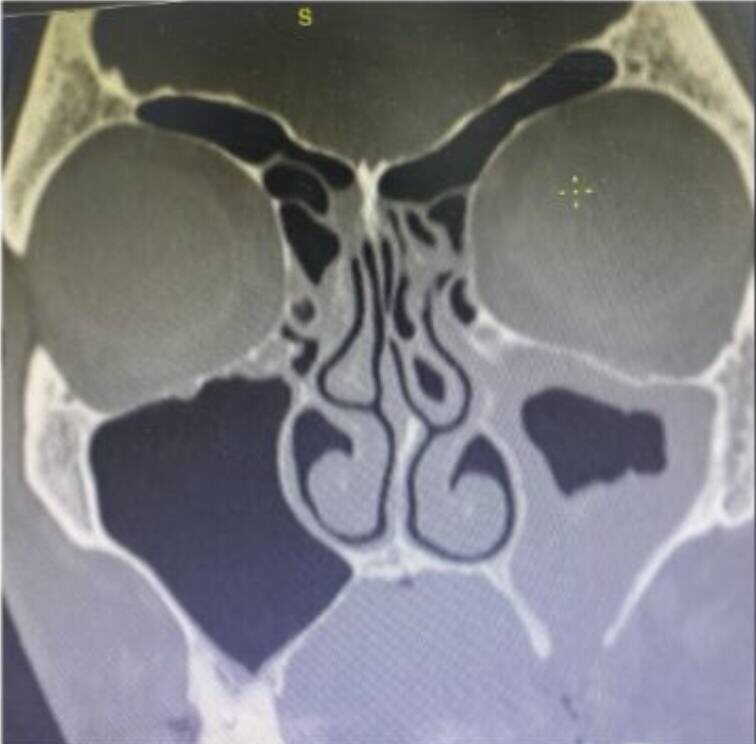

➡️По данным КТ: искривление перегородки носа, снижение пневматизации левой верхнечелюстной пазухи, сoncha bullosa слева. Дефект нижней стенки в/ч пазухи.